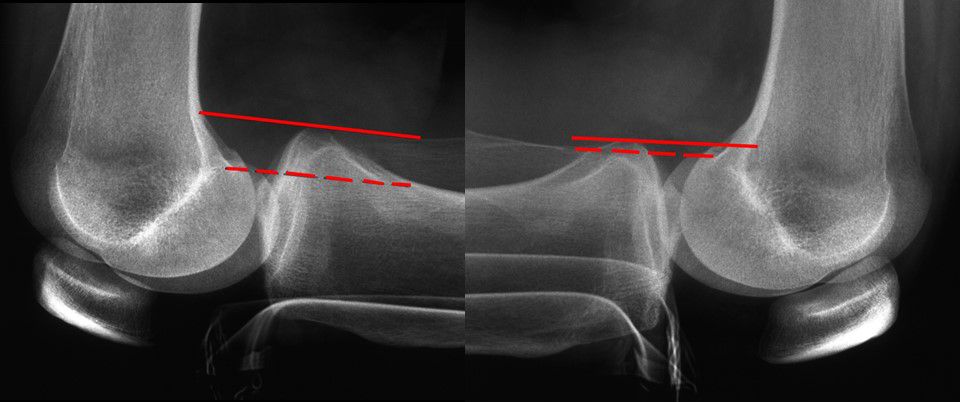

This is followed by stress x-rays routinely. In contrast to Telos used stress x-rays we prefer the kneeling view according to Bartlett which does not allow muscular compensation of the instability (Fig 2). MRI is also performed routinely to get information about the personality of PCL rupture and associated lesions.

Fig 2 - Bartlett Stress View bilateral